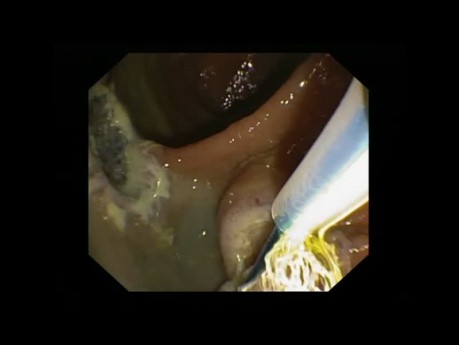

Mukozektomia endoskopowa (EMR) guza LST-G esicy...

W filmie pokazano polipektomię u 72-letniego pacjenta przyjmującego warfarynę. W endoskopii uwidoczniono guz LST-G esicy o wymiarach 45x25 mm. Wykonano EMR w kawałkach.